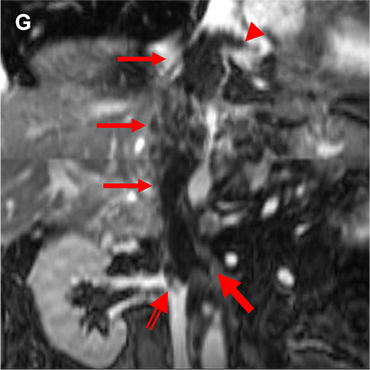

図2.ガドビスト造影MRI (A:T2WI B:DWI(b=800) C:ADCmap D:造影前脂肪抑制T1WI E:造影後脂肪抑制T1WI F:造影後True FISP G:造影後TrueFISP冠状断像)

(A-F→)下大静脈内の腫瘍はT2WI低信号で、DWIで不均一な高信号、ADCは軽度低下している。hypovascularであり、造影True FISP冠状断像で頭側は右房内(➤)、尾側は右腎静脈起始部(⇒)、左腎静脈(➔)に及んでいることがわかる。

転移性肝腫瘍の経過観察でプリモビストMRIを行っており、心臓超音波後、hypovascularな下大静脈内腫瘍がプリモビストMRIでも確認された。腫瘍進展範囲の精査としてガドビストMRIを施行。Slow infusion造影(6倍希釈した造影剤を6分間流し続ける)のTrue FISPを加え、腫瘍周囲の血管を乱流の影響を抑え、常に高信号に描出することでhypovascularな腫瘍の正確な進展範囲が評価可能であった。